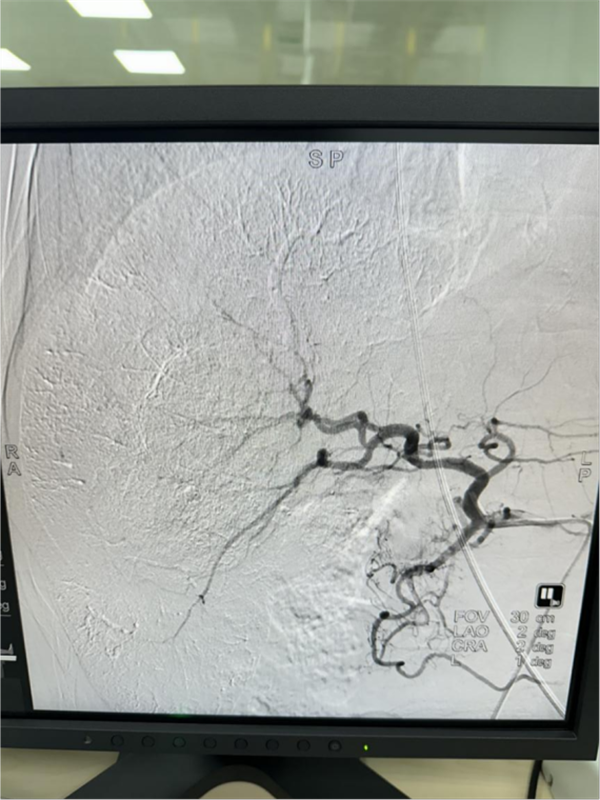

手术全程顺利,栓塞效果满意,有效控制肿瘤。肝癌是我国最常见的恶性肿瘤之一,早期症状一般不明显,等有症状再来医院就诊时,通常都是中晚期,大部分患者都失去了外科切除的机会,这个时候,介入治疗成为了控制肝癌的最常用手段。肝癌介入治疗(TACE)的核心原理,就是通过给肝癌提供营养的血管直接注入药物到癌细胞,然后堵塞营养血管,在杀灭癌细胞的同时,让癌细胞没有血流供应。

术后造影